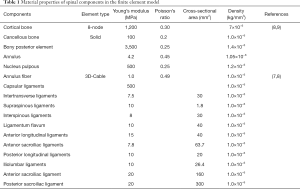

Assigning values to the model; using ABAQUS finite element analysis software for processing and analysis: in this experiment, another value assignment method in the finite element software was used, that is, the materials were assigned values taken from the parameters in past studies. The material properties of all tissues were considered homogeneous and isotropic (Table 1).

Full table

Note: for the parameters of this model, please refer to the table above, which are the same except those for the sacroiliac ligament, iliolumbar ligament, and density.

These ligaments were all simulated with Truss elements according to their function, and the properties of the Truss elements were defined such that there was no elastic force when compressed but there was elastic force when stretched; that is, the ligament elements only had tensile load. The number of Truss units was determined according to the cross-sectional area of the ligament, and in order to avoid concentrated local stress, the following settings were chosen: 20 anterior longitudinal ligaments, 20 posterior longitudinal ligaments, 16 interspinous ligaments, 12 supraspinous ligaments, 32 intertransverse ligaments, 20 ligamenta flavum, and 48 capsular ligaments, for a total of 168 Truss units. In the motion between lumbar facet joints, there were relative changes in position and friction, so we set this motion as an interaction, and the friction coefficient was defined as 0.2.